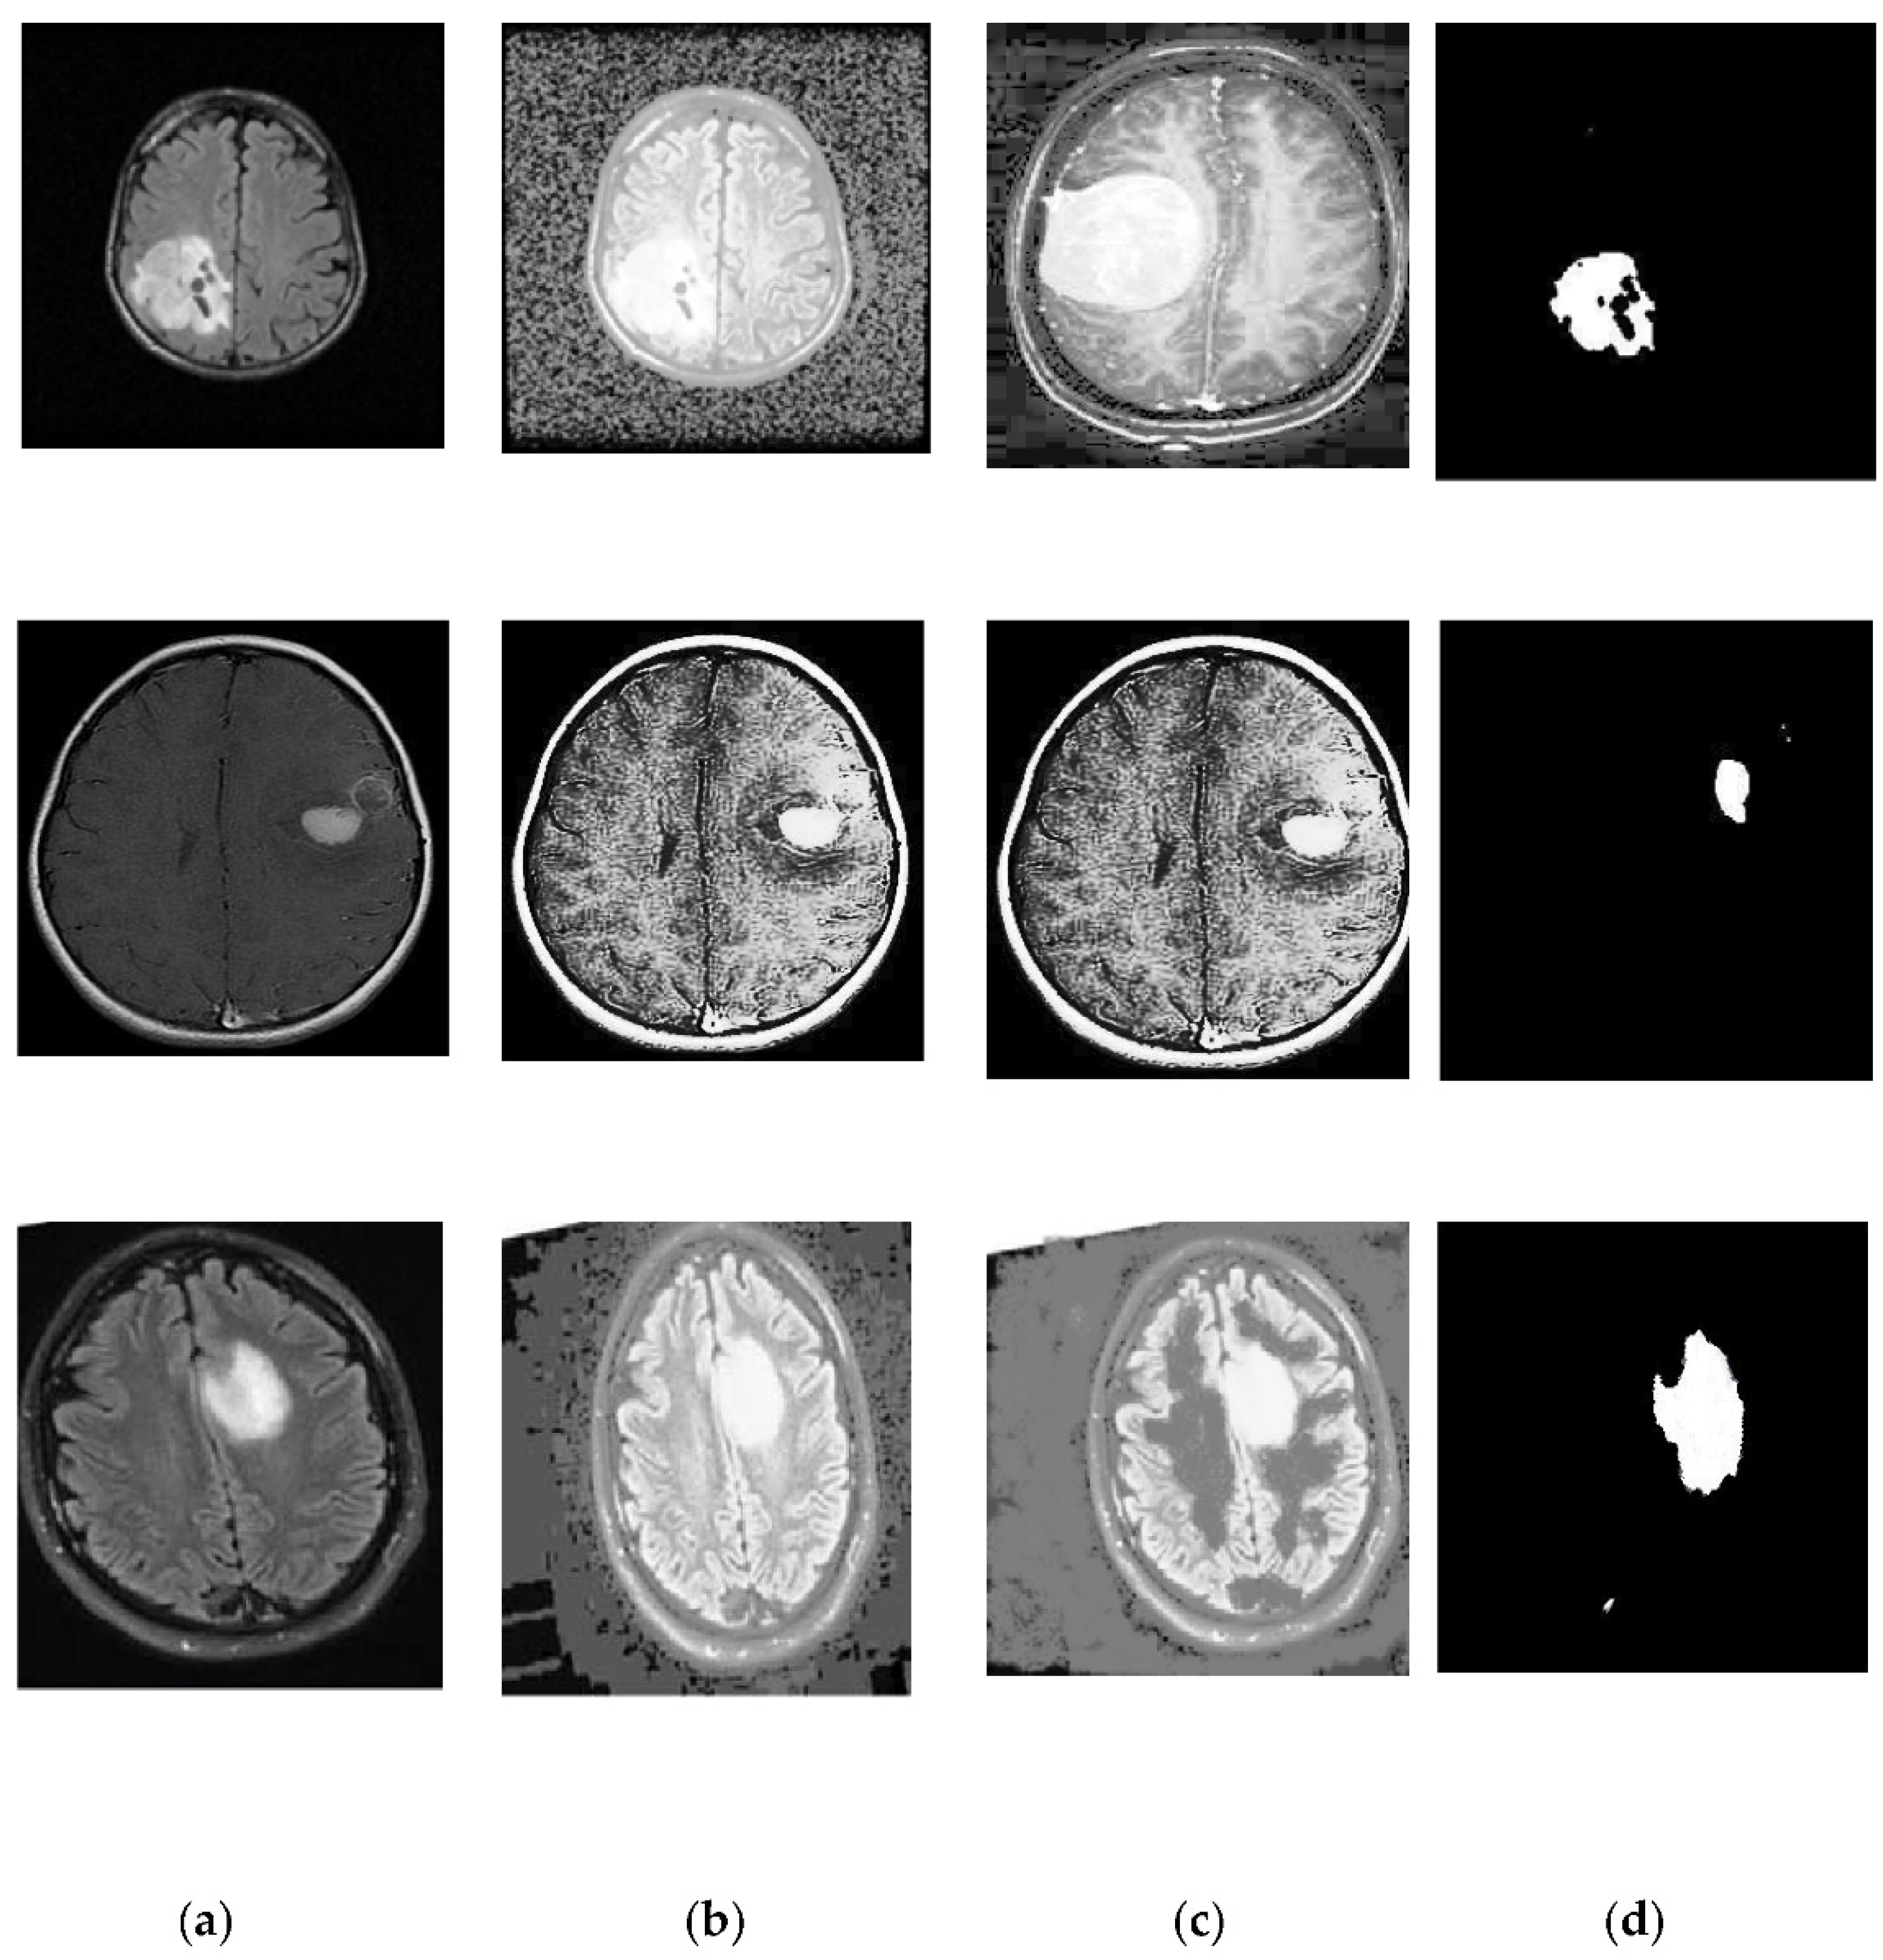

2.3. Segmentation